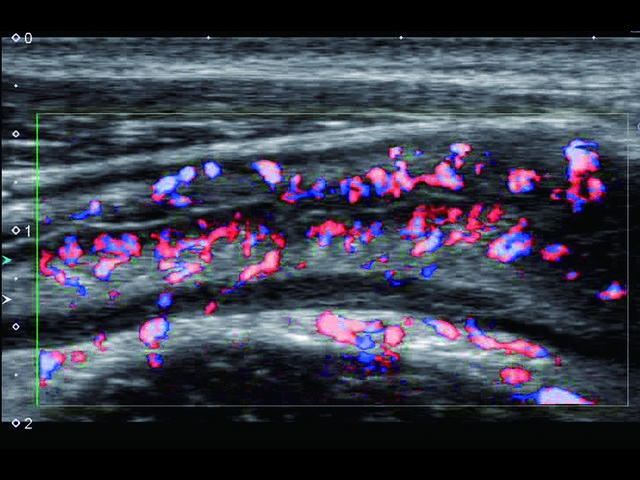

Обновленная версия легендарного УЗ-сканера. Стационарный аппарат экспертного класса Aplio 500 Toshiba NEW, визуализирует анатомические структуры в высоком разрешении. Модель позволяет выявить микрокальцификаты, новообразования, нарушения в работе сердца, сосудов и мышц. Присутствует функция виртуальной эндоскопии, 4D-сканирования, эластометрии тканей, УЗИ с контрастированием. За повышение качества изображения отвечают технологии ApliPure и Superb Microvascular Imaging. Первая задействует возможности пространственного и частотного кодирования, формирует цельный визуальный ряд с сохранением клинических маркеров. Вторая улучшает отображение микрососудистого русла, используя доплеровский эффект. Модель оснащена 21-дюймовым монитором, имеет 4 активных порта. Возможно подключение педиатрических, интраоперационных, лапароскопических и чреспищеводных датчиков.

• SMI. Опция, упрощающая визуализацию микроциркуляторного русла. С ее помощью обследуются сосуды с низкой интенсивностью кровотока, изучаются наиболее тонкие структуры. SMI упрощает диагностику новообразований, минимизирует вероятность ошибки.

Энергетический допплер:

Да

Цветовой допплер: